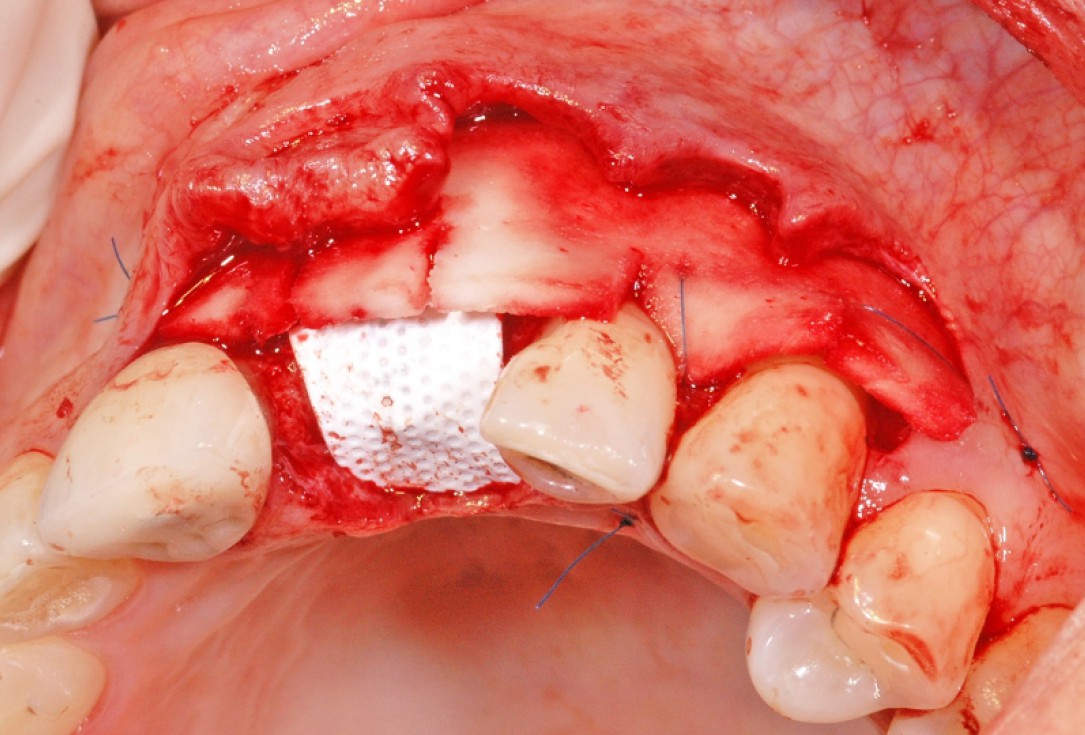

6/18 - Augmentation with maxresorb® and covering with a non-resorbable PTFE membraneGBR together with soft tissue augmentation with mucoderm® and maxresorb® - Dr. S. Scherg

7/18 - Fixation of the membrane with titanitum pinsGBR together with soft tissue augmentation with mucoderm® and maxresorb® - Dr. S. Scherg